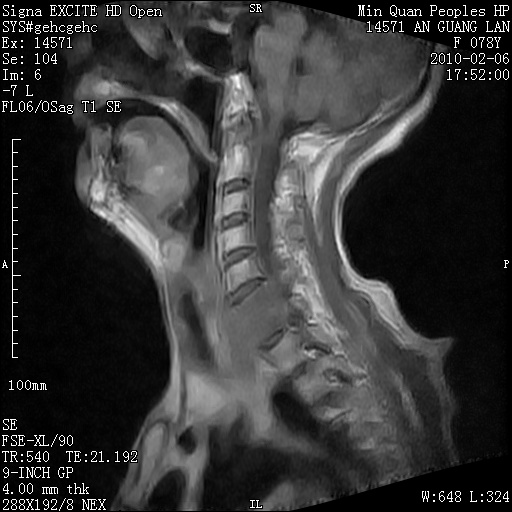

标题: MRI2763:C6、C7椎体病变性质?

f,78y,颈部与双上肢阵发性剧痛40余天。ct可见c6、c7椎体虫蚀样破坏,其间椎间隙变窄(没有图片资料可供上传)。

考虑椎体结核并椎旁脓肿。

支持 c6、7椎体结核并椎旁冷脓肿形成。

考虑:c6/7椎体结核并椎旁脓肿形成,建议增强扫描。